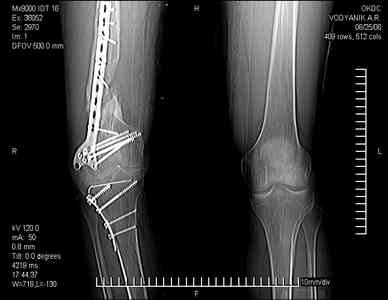

Тугой ложный сустав правого бедра в сочетании неправильно сросшимся переломом большеберцовой кости |

Уважаемые коллеги,В ортопедическое отделение обратился пациент: мужчина 47 лет, который в течение 4-х лет дваждыполучил травму костей, образующих правый коленный сустав. В 2002 v внутрисуставной оскольчатыйперелом проксимального метаэпифиза правой большеберцовой кости; в 2005 v внутрисуставнойоскольчатый перелом дистального метаэпифиза правой бедренной кости. В обоих случаях в разных лечебных учреждениях проводилось оперативное лечение переломов.При осмотре в отделении на основании результатов клинического осмотра и данных визуальныхметодов обследования поставлен диагноз:тугой ложный сустав дистальной трети правой бедренной кости, состояние после накостногоостеосинтеза перелома типа 33-В2.2 ; несросшийся перелом надколенника; неправильно сросшийсяперелом латерального мыщелка правой большеберцовой кости, состояние после металлоостеосинтезаперелома 41-В2.2; сочетанная осевая деформация правой ноги: варусная деформация правого бедра,вальгусная деформация правой голени; посттравматический артроз коленного сустава 4 ст по Kellgren-Lowrence; выраженное нарушение функции ходьбы и опоры. Внешний вид ноги больного, данные рентгенографического обследования и избирательно выделенные компьютерные томограммы приведены в приложении. В именах КТ использовано кодирование уровня по АО, т.е. _41, например, означает проксимальную треть голени.В отделении намечен v очень предварительно v следующий план лечения: 1. Иметь ввиду перспективу тотального эндопротезирования коленного сустава. 2. С учетом п.1 при проведении действий, направленных на устранение ложного сустава бедренной кости не использовать материалы, не подвергающиеся трансформации. 3. В ходе операции, направленной на устранение ложного сустава: А. удалить все металлоконструкции; Б. ревизовать зону пролежня под пластиной на бедре, при наличии признаков достаточной жизнеспособности кости выполнить остеопериостальную декортикацию, дрилинг ложа пластины; В. Удалить рубцовую ткань по плоскости ложного сустава, и в пространстве между костными форагментами, насечь обращенные друг к другу поверхности. Ввести штифт с блокированием (например Stryker с учетом особенностей расположения дистальных блокирующих винтов у этойконструкции). Осуществить остеосинтез с учтанением варусной деформации бедренной кости. Пространство в зоне ложного сустава и пустоты в метафизе бедренной кости заполнить резорбирующимся цементом на основе гидроксиапатита кальция. Для дистальной фиксации использовать винты с переменным шагом резьбы. Вариант:, винты вводить после заполнения метафиза цементом. Дополнительные виды создания межфрагментарной компрессии во встречно-боковом направлении обсуждаются. Г. Быть готовым к кровопотере. Д. Учесть высокий риск инфекции, тромбоэмболических осложнений. Е. Вопрос о внешней иммобилизации решить по результатам оценки стабильности остеосинтеза. Вариант - одноосевой стержневой аппарат для шунтирования гвоздя с модулем на голени и дистракцией коленного сустава в течение 3-5 недель. Просим вашей критики намеченного плана и конструктивных предложений. С уважением к сообществу, Ординатор В.С. Саплин